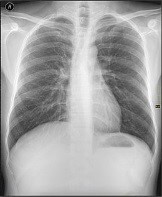

- Radiographie pulmonaire : 0,02 mSv